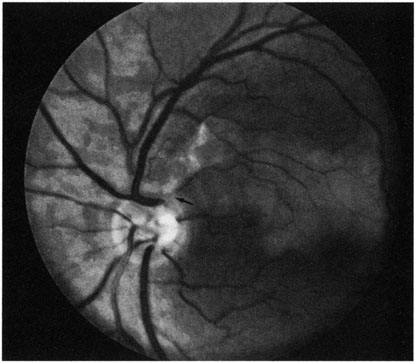

Ophthalmic artery obstruction is characterized by an initial opacification of the entire retina in a manner similar to that of central retinal artery obstruction (Fig. 4A). The cherry-red spot may or may not be present, however.119 The difference between an ophthalmic artery obstruction and central retinal artery obstruction is that in an ophthalmic artery obstruction, with time, optic atrophy develops, as does varying amounts of pigmentation due to the lack of perfusion of the retinal pigment epithelium (see Fig. 4D). This pigment is generally diffusely scattered throughout the posterior pole but it may also be seen in greater amounts in the periphery.

Intravenous fluorescein angiography generally shows moderate to marked abnormalities in the filling of the choroid, in addition to a delay in filling or even nonfilling of retinal vessels (see Fig. 4B and 4C). Staining of the retinal pigment epithelium can also be seen; this staining either can occur locally in the macular area or it can be diffuse.119 The electroretinogram shows abnormalities of both a- and b-waves, reflecting ischemia to both the inner and outer retina. Almost all reported patients have had an initial visual acuity of no light perception; virtually no patients can be expected to have a final visual acuity better than that.119 An acuity of no light perception is a clue to the presence of an ophthalmic artery obstruction. Because relatively few patients with central retinal artery obstruction have an initial visual acuity of no light perception, no light perception usually suggests the likelihood of some obstruction of the choroidal circulation.14